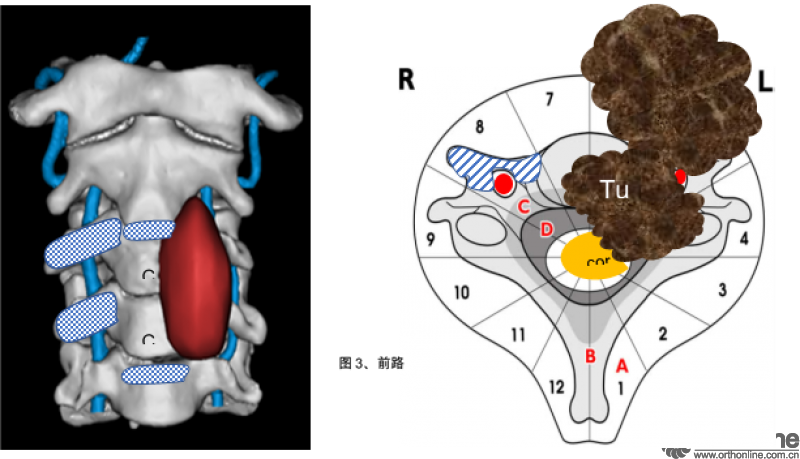

根据术前的影像学显示,肿瘤累及C3-4椎体、在左侧椎间孔形成软组织肿块包绕左侧椎动脉、C3和C4神经根,并且向椎管内和左侧颈长肌蔓延。肿瘤的恶性程度要求必须将肿瘤连同受累的所有结构作为一整块地切除。切除的范围不充分,切除过程中肿瘤的包膜有破损,都容易造成肿瘤的复发。但牺牲左侧的C3和C4神经根势必造成术后左侧膈肌麻痹;切除左侧椎动脉则有脑梗的风险。在充分评估肿瘤彻底切除的必要性、手术风险,以及和病人充分的沟通后,我们拟定了如下整块切除的手术计划。

首先从前方入路,切除C2-3和C4-5椎间盘及后纵韧带,切除C3和C4右侧横突孔,游离右侧的椎动脉,切断左侧椎旁肿瘤近端和远端的颈长肌,游离椎旁软组织的肿瘤。

随后,行后正中入路,做C1侧块,C2、C5、C6椎弓根螺钉固定。分块切除C3和C4没有被肿瘤累及的附件结构,将肿瘤在椎管内外的部分充分游离,,在硬膜外切断左侧C3和C4神经根。

最后再从前方原手术切口进入。切断左侧椎动脉、将C3、C4椎体及椎旁的肿瘤作为一整块地取出。C2-5椎体间放置3D打印人工椎体后用钛板固定。